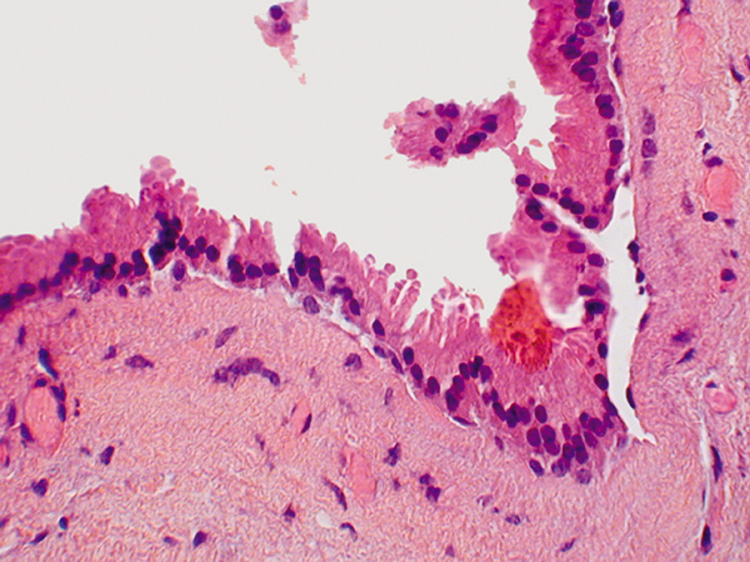

Histologically, the epidermis shows papillomatosis and cystic invaginations into the dermis. Papillary projections lined by two rows of glandular epithelium extend into the lower portion of the cystic spaces (Fig. 39). The luminal row of cells are columnar and may show decapitation secretion, whereas the inner row of cells are small and cuboidal. A characteristic feature of this tumor is a dense plasmacytic infiltrate in the stroma, especially the papillary projections.

Fig. 39. Syringocystadenoma papilliferum. A. Clinical appearance of lesion. B. Numerous cystic spaces in the dermis contain papillary projections. C. Apical (decapitation) secretion from the papillary projection with a dense plasmacytic infiltrate in the stroma.